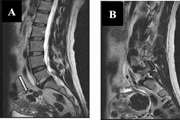

Renal Sympathetic Denervation by CT scan Guided Periarterial Ethanol Injection in Sheep

To evaluate the feasibility, efficacy, and complications of computed tomography (CT)-guided periarterial ethanol injection